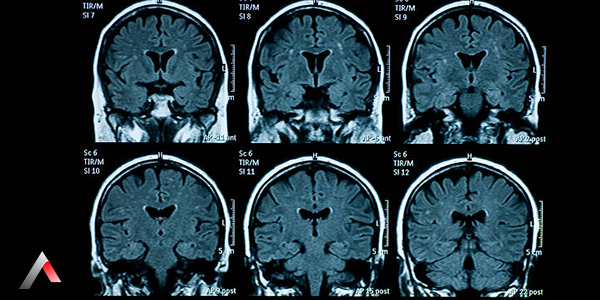

Beyin MR Görüntüsü

Beyin_MR_G__r__nt__s___0c20da06.webp